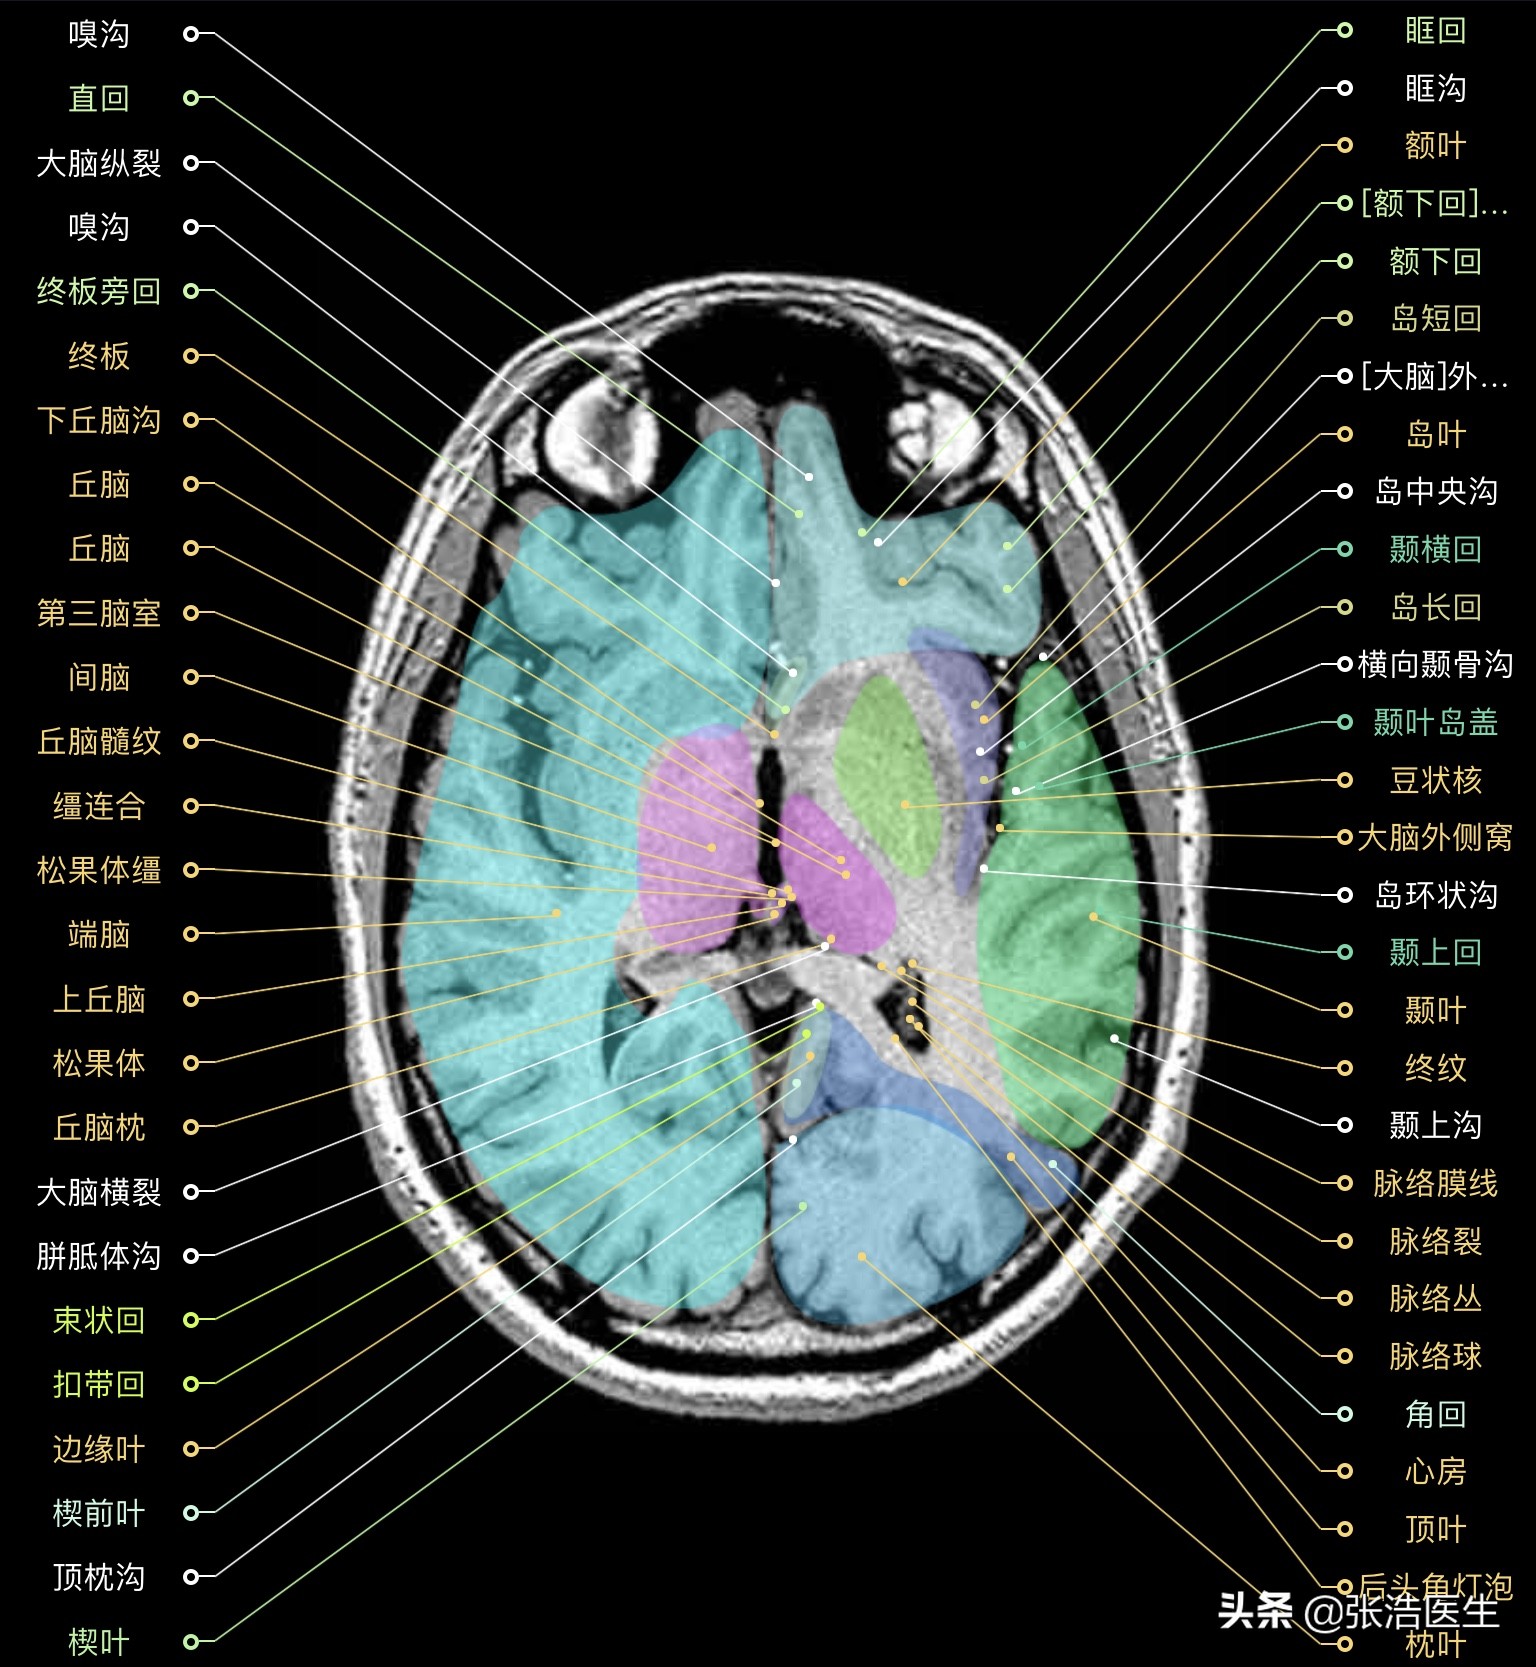

颅脑MRI横断面高清解剖图谱(图层5)